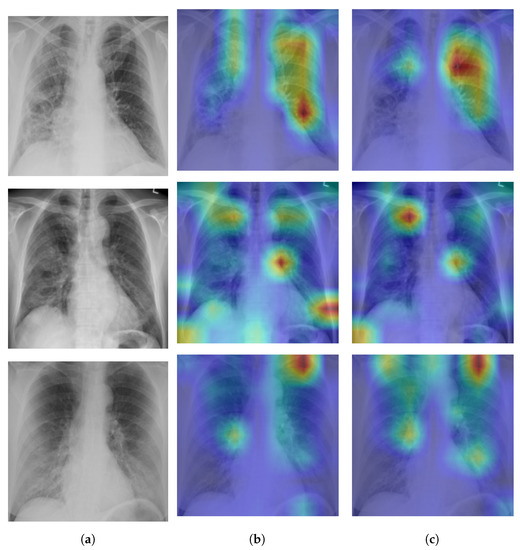

Figure 3 shows examples of SIIM-COVID-19 and RSNA CXR images.

Figure 3. Examples of BIMCV COVID+; (a,b) and NIH; (c,d) CXR images.